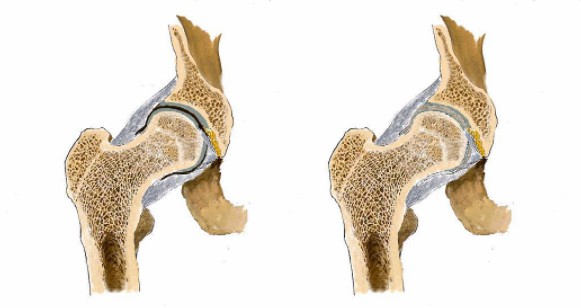

看男孩不說(shuō)話,醫(yī)生繼續(xù)說(shuō)道:“你的HLA-B27顯示陰性,如果是陽(yáng)性就可以確診是強(qiáng)直性脊柱炎,現(xiàn)在只能排查……如果確診是強(qiáng)直性脊柱炎,就要就要及早治療,因?yàn)檫@個(gè)病是不可逆的,我們只能延緩它病程進(jìn)度……”

醫(yī)生對(duì)著拍好的片子來(lái)來(lái)回回看了好幾遍,男孩就一直站在他邊上,他知道醫(yī)生接下來(lái)說(shuō)的話將決定自己的一生。